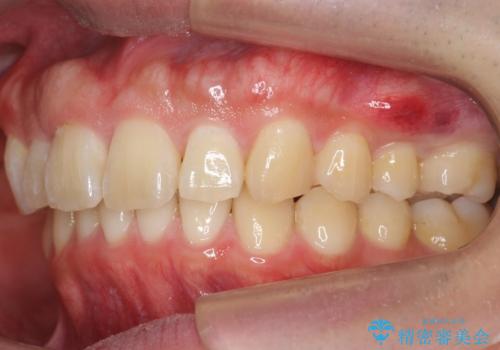

出っ歯を治したい 深いかみあわせ インビザラインで治療

上顎は歯を抜かずに、奥歯を後ろに下げる治療を行っています。

下顎は歯列を拡大して並べました。

歯を抜かずに奥歯を後ろに動かすために、矯正用のミニスクリューを使用しています。